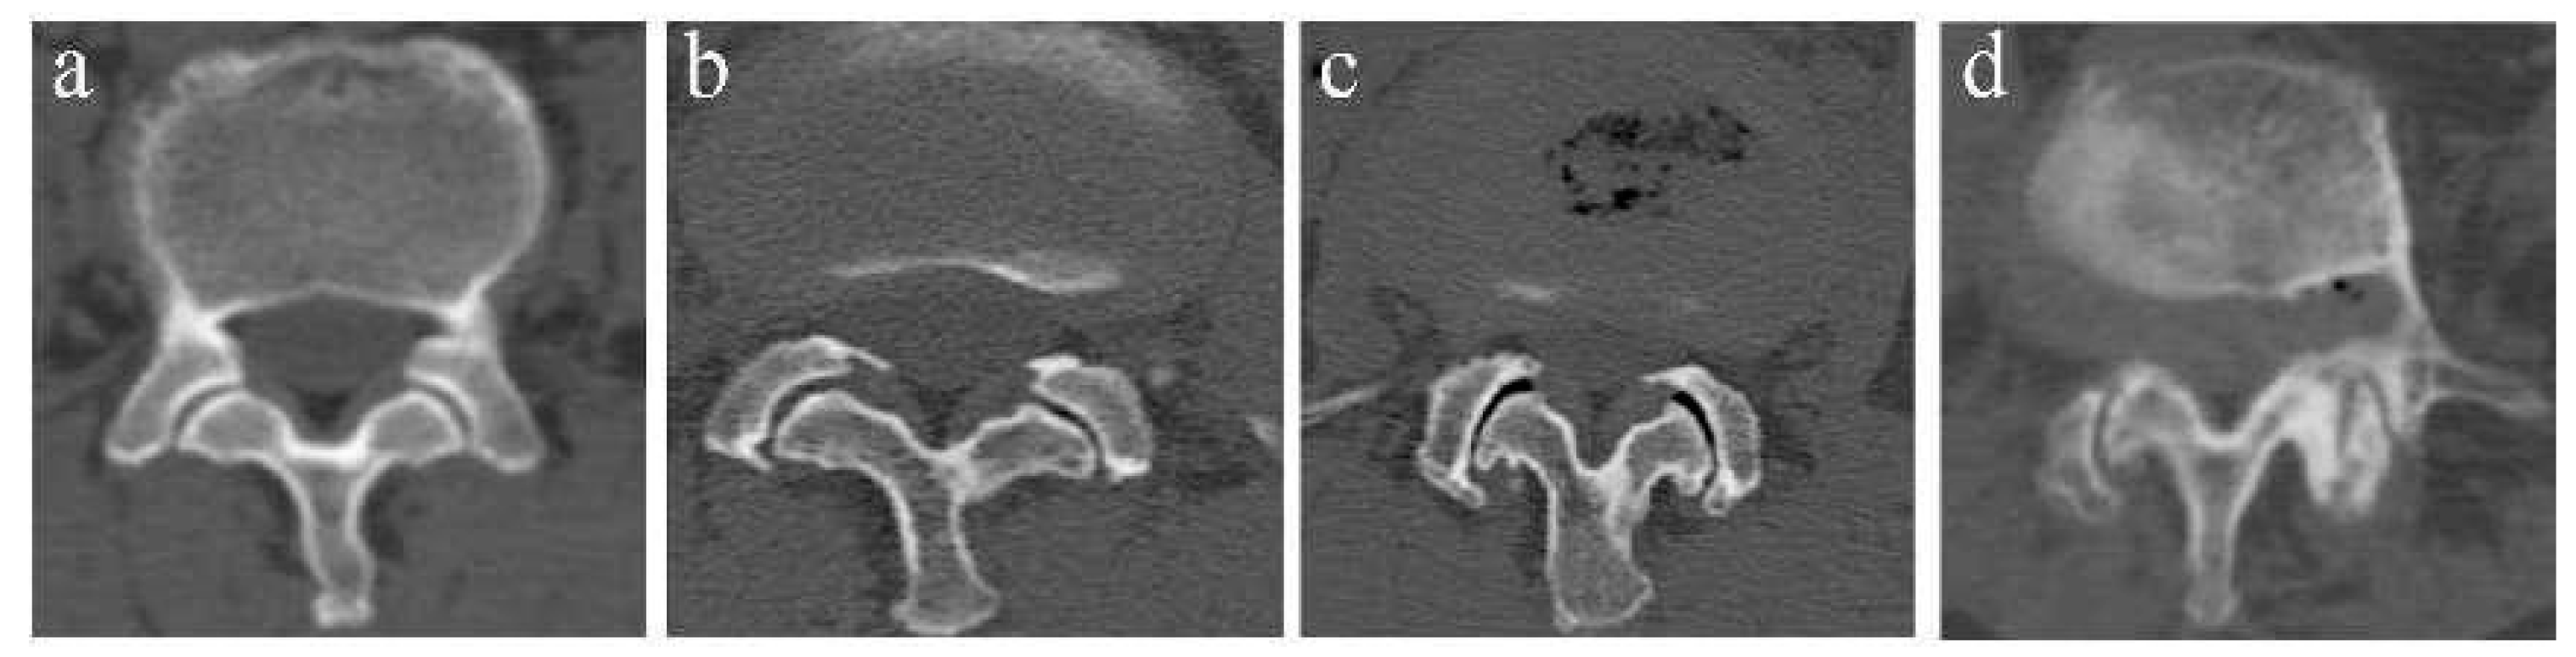

2.4.4. Evaluation of PVM Change

The multifidus muscle (MM) has been the most studied and commonly used measurement with which to evaluate the fat infiltration and atrophy of PVM [11,12]. The percentage of the fat infiltration area (%FIA) was measured via axial T2-weighed imaging at the L4-L5 disc level by using ImageJ software (Version 2.0.0, National Institutes of Health, Bethesda, MD, USA). First, we converted each image into a grayscale 8-bit image. We then outlined the region of the multifidus muscle using the threshold technique and utilized a “default” and “dark background” method to obtain the value of the threshold automatically. Last, we calculated the %FIA; the red area in the 8-bit image was the fat tissue, and the fat tissue divided by the region of the multifidus muscle was the %FIA (Figure 4) [13].

Figure 4.

Example of fat tissue (red color) of the MM showed in the ImageJ software (Version 2.0.0, National Institutes of Health, Bethesda, MD, USA).